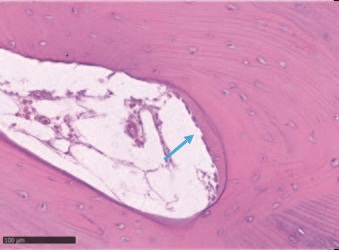

Гистологический анализ показал хорошо организованную, в основном зрелую ткань, образованную компактной пластинчатой костью с четко очерченными костными пластинками вокруг каналов Гаверсияна и Фолькмана, окруженных меньшими участками, в которых пластинки были менее организованными и богатыми остеоцитами на стадии созревания. Количество минеральной матрицы - от 69% до 72% - было особенно значительным. Воспалительного инфильтрата не наблюдалось.

Рис. 10 – Как видно, в некоторых медуллярных областях происходит отложение нового костного матрикса (синяя стрелка). Кость в пластинчатой форме свидетельствует о развитом состоянии созревания ткани.